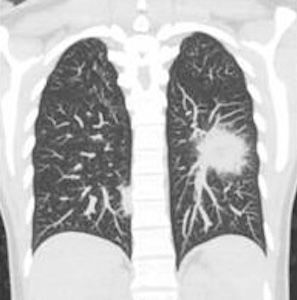

Lung cancer screening is a medical test that detects lung cancer in its early stages before symptoms appear.

A Lung Cancer Screen is typically performed using a low-dose computed tomography (LDCT) scan, a specialised type of X-ray that creates detailed images of the lungs.

- Lung Nodules: Small growths or lumps in the lungs that may or may not be cancerous.

- Lung Nodules: Small abnormal growths that could be benign, pre-cancerous, or cancerous.